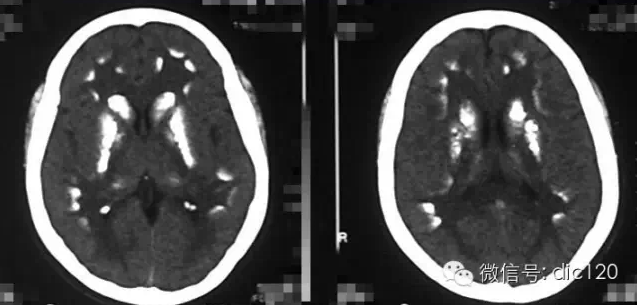

診斷小腦萎縮通常需要進(jìn)行神經(jīng)系統(tǒng)檢查、影像學(xué)檢查(如腦部CT或MRI)和實(shí)驗(yàn)室測(cè)試,治療小腦萎縮的方法主要包括藥物治療、物理治療和康復(fù)訓(xùn)練等,藥物治療旨在緩解癥狀和改善生活質(zhì)量,物理治療幫助患者恢復(fù)肌肉力量和運(yùn)動(dòng)功能,康復(fù)訓(xùn)練則包括語言治療、認(rèn)知訓(xùn)練和心理支持等。